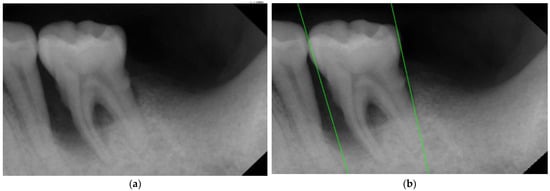

2.2.2. Rote Tangent

| Original Images | Gaussian High-Pass Filter | Gaussian High-Pass Filter + Mask | |

|---|---|---|---|

| Validation Accuracy | 84.16% | 87.21% | 94.97% |

| Validation Loss | 0.7634 | 0.4578 | 0.1822 |

| Image | ![]() | ![]() | ![]() |